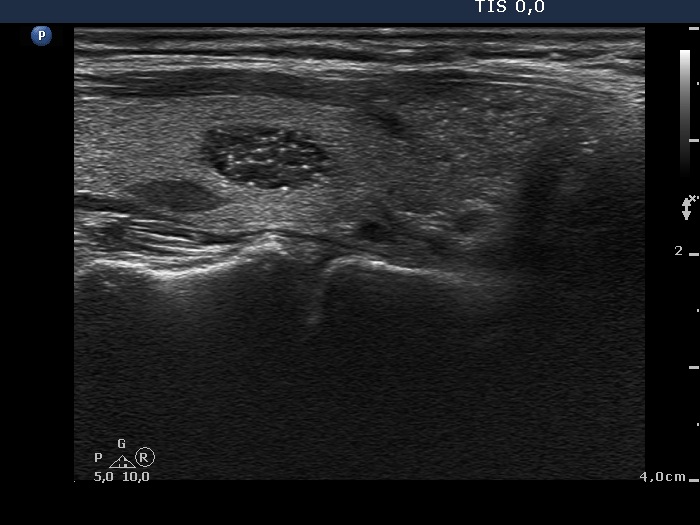

Follicular adenoma (histological diagnosis) - case 1056 |

Papillary carcinoma (histological diagnosis) - case 1074 |

The presentation of the granules is similar in these cases. However the benign lesion has several granules with dorsal tail, therefore these correspond more likely to comet-tail artifacts than to punctate echogenic foci. On the other hand, the complex structures in the malignant nodules are composed of multiple granules. It is worth comparing the figures marked with arrows.